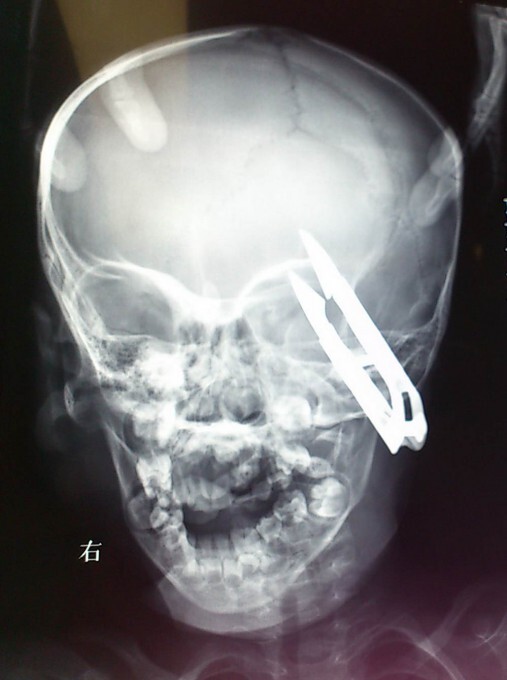

2-летний мальчик чудом выжил после того, как ножницы пронзили его голову в районе глаза. Ван Жиеронг из западной китайской провинции Ганьсу бегал по дому с ножницами, которые он нашел на столе. Неожиданно он споткнулся и упал прямо на ножницы, которые вонзились ему прямо над левым глазом

Мальчика сразу доставили в больницу университета Ланьчжоу в округе Вушань, где врачи провели срочную операцию по удалению ножниц.

Жиеронг все время находится под пристальным наблюдением медицинского персонала с того самого момента, как он поступил в больницу. Врачи сообщают: «В будущем у мальчика не должно быть, ни каких проблем с данным инцидентом».

Вероятно, мальчик родился в «рубашке», падение с силой на ножницы могло привести к смертельному исходу.